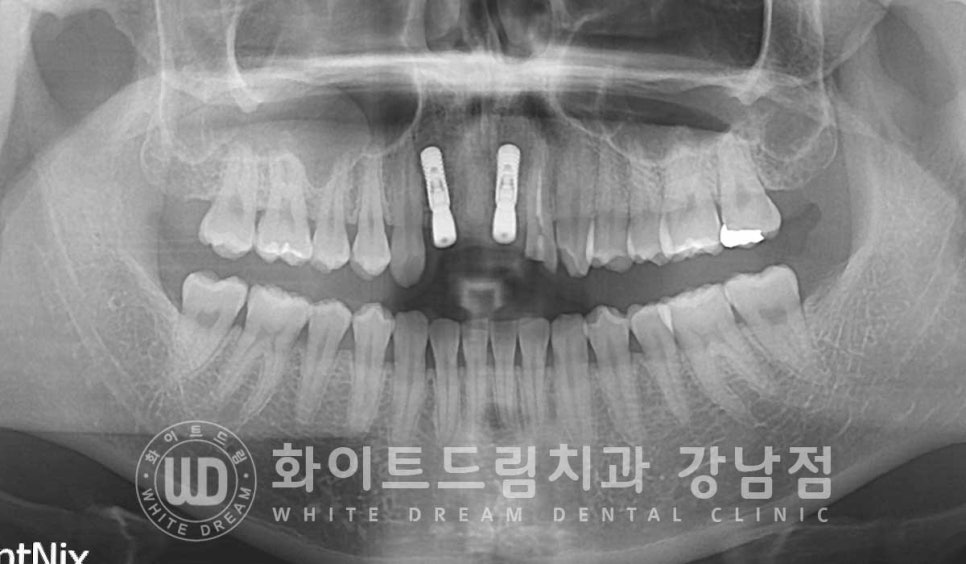

▲ 앞니 3개가 사고로 탈구된 상태 / 앞니 빠짐 임플란트

오늘은 교통사고로 앞니가 탈구되신 환자분의 치료 사례와 함께

앞니 임플란트 치료에 대해서 이야기를 나눠보겠습니다.

환자분의 초진 x-ray 사진입니다.

상악 앞니 3개(22, 21, 11번 치아)가 빠져있고

그 옆 22번 치아는 치아머리 반이 부러진 상태입니다.